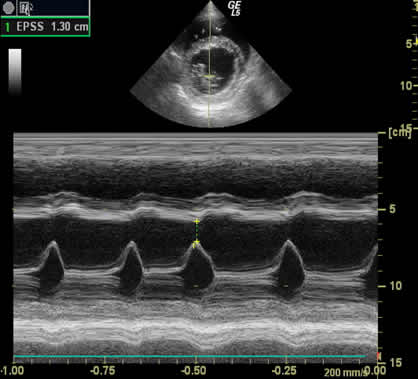

• Ecocardiograma (ultrasonido de corazón).

En nuestra clínica contamos con equipos diagnósticos adecuados para abordar y diagnosticar estas enfermedades, por ejemplo electrocardiograma, rayos x, ultrasonido y una preparación constante en esta área. Además tenemos un servicio anexo de cardiología para abordar enfermedades complejas y que necesitan equipos de diagnostico y conocimientos mas especializados.